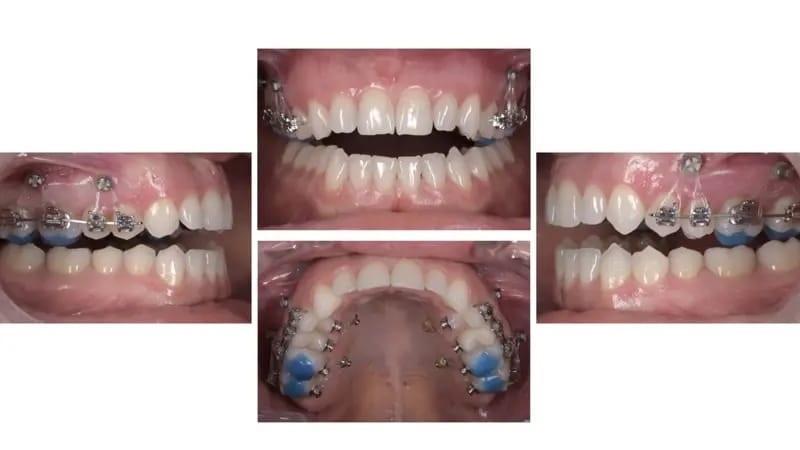

Была выбрана сплинт-шина, состоящая из двух частей, ее можно носить 24 часа в сутки в заднем сегменте днем и в переднем сегменте ночью (фото 23). Лечение шинами продолжалось в течение четырех месяцев, в течение которых было достигнуто стабильное положение мыщелков, пациентка добилась одномоментного закрывания рта и была достигнута полная ремиссия симптомов ВНЧС. В результате ротации нижней челюсти изменился прикус, что привело к увеличению переднего открытого прикуса (фото 24), увеличенное горизонтальное перекрытие верхних и нижних передних зубов (фото 25) и улучшение челюсти до классификации II класса (фото 26).

Фото 26a–c: Виртуальный артикулятор, показывающий окклюзионные изменения после наложения шины.